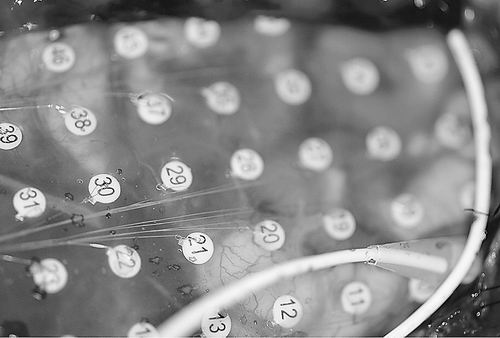

电极检测癫痫患者的大脑活动。图片来源:GORDON BALTUCH

两个研究小组都以癫痫患者的神经活动为研究起点,这些患者都接受过大脑修复手术。神经科学家Michael Kahana是Penn小组的领导者,他说,对于其中一些患者,研究者必须为他们的大脑覆盖上数百个电极,并等待数周直到患者再次发病,之后才能决定从哪个大脑区域下手进行治疗。通过这种方法,研究者能够精确地绘制一张大脑活动图,了解与记忆储存和修复相关的电生理学知识。电子记录还能帮助研究者对记忆缺陷有更深刻的了解,许多癫痫患者都饱受记忆缺陷之苦。